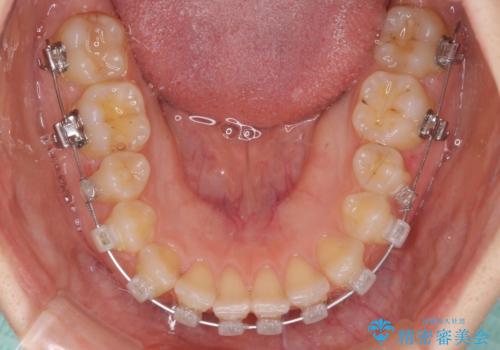

- 矯正装置

- クリアブラケット

結婚式の予定があり、可能であれば結婚式までに治療を終えたいとのことで、短期間で治療をおける可能性の高いワイヤー装置にて矯正治療を行うこととしました。

ギリギリとなりましたが、結婚式直前にワイヤー装置を外すことができました。